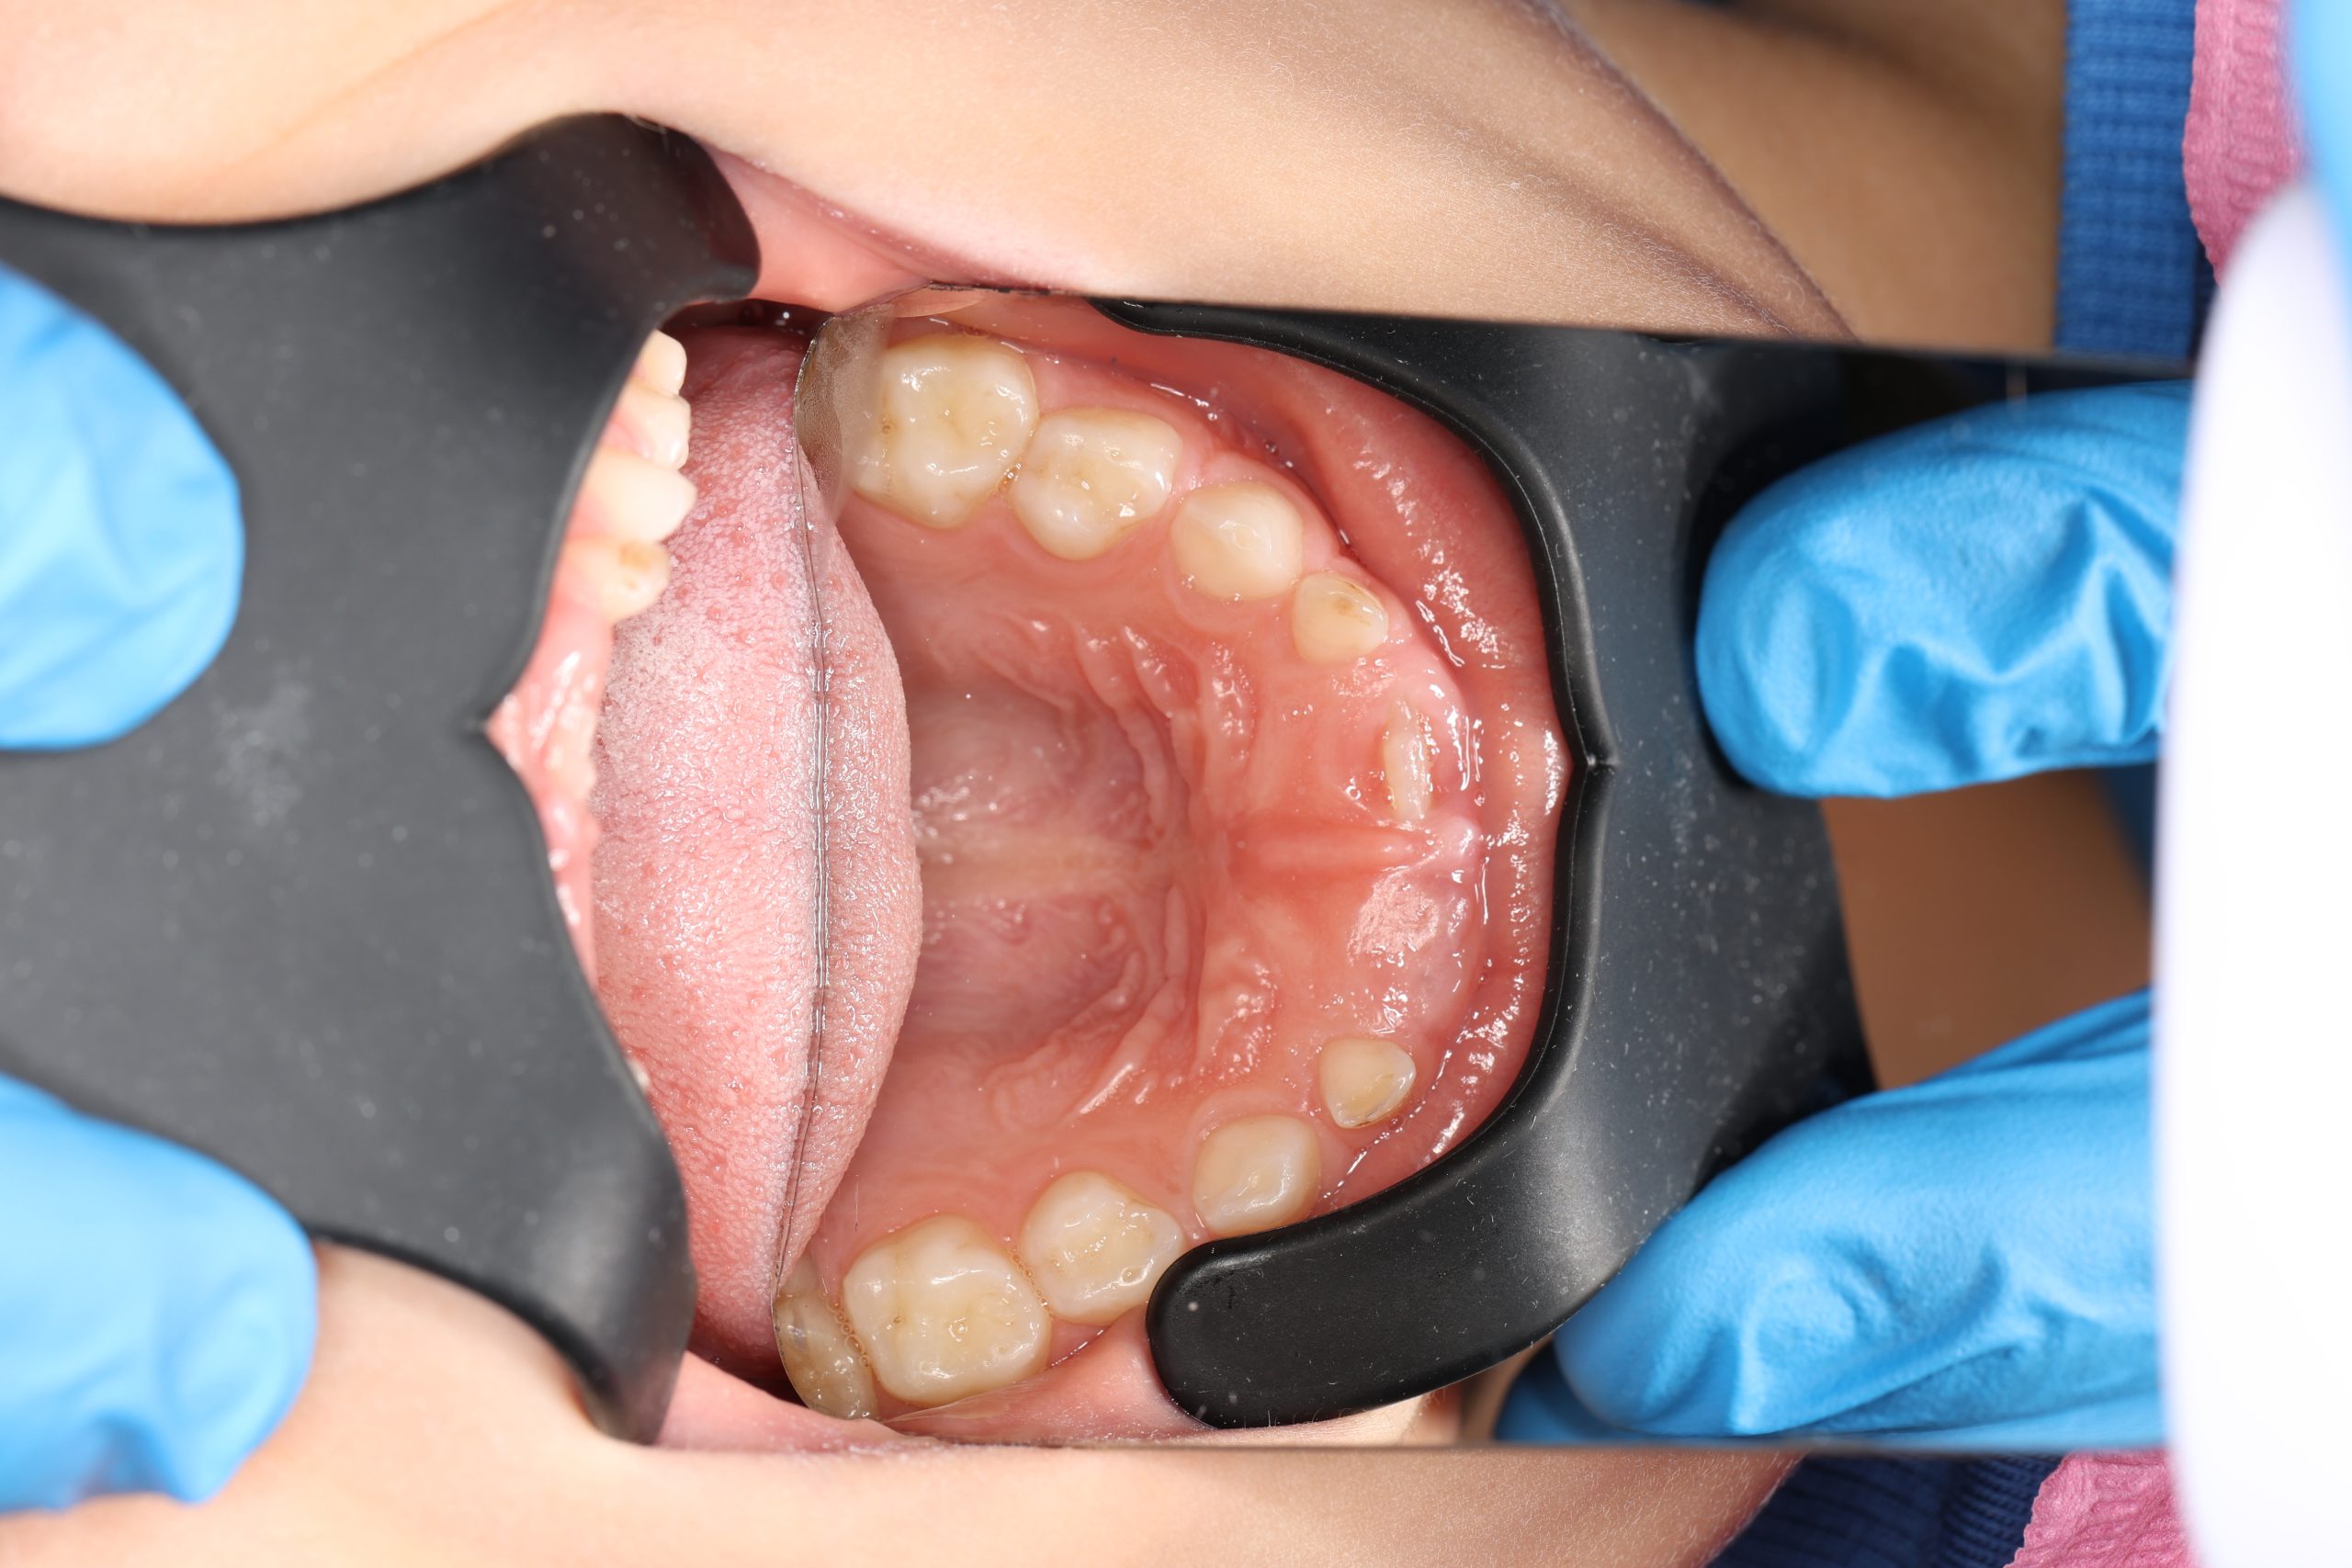

We examine the condition of teeth, gums, and bite. - Plaque Disclosure with Special Indicators

Areas that weren’t cleaned well appear purple. The darker the shade, the older the plaque. This helps both kids and parents understand where brushing needs to improve. - Brushing Training & Home Care Tools Selection